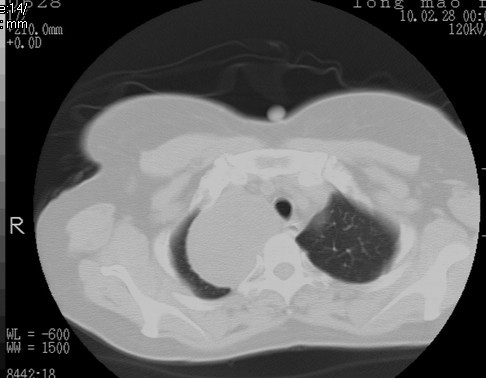

以下是引用随光逐影在2010-3-1 8:36:00的发言:[br]右上纵隔囊性占位性病变,考虑支气管囊肿,不排除神经源性肿瘤。